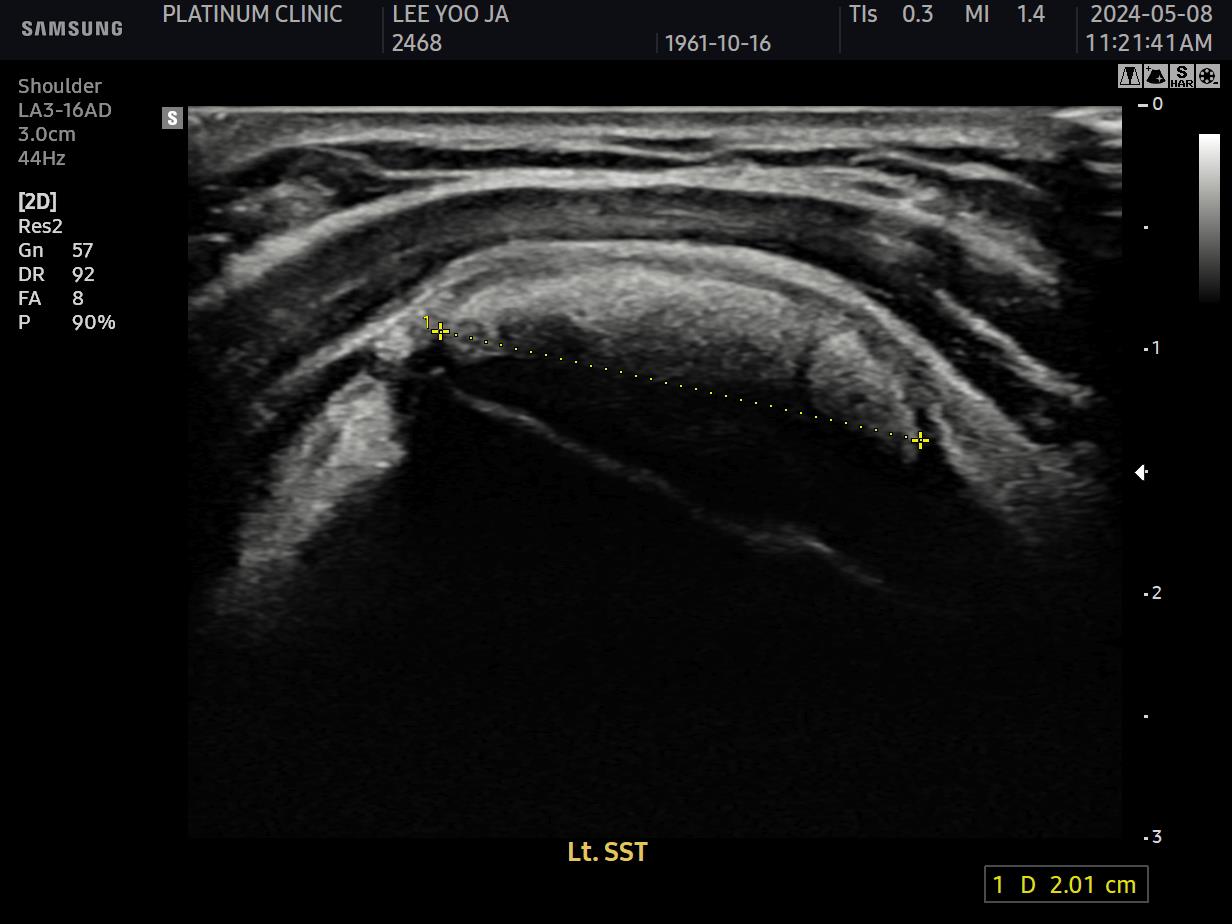

2) 근본적인 문제 해결: 석회분쇄흡입술

근본 원인인 석회를 제거했습니다. 초음파로 확인된 미세석회들을, 석회분쇄흡입술을 통해 힘줄 사이사이에서 씻어내듯 제거했습니다.

초음파 검사에서도 석회는 깨끗이 사라졌고, 관절낭 유착도 재발하지 않았습니다.